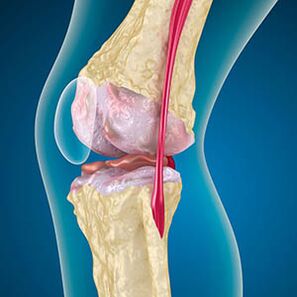

Com a artrose, a cartilagem revestindo as bordas dos ossos é abrasão ou completamente ausente. O tecido danificado não é uma fonte de dor, porque não possui receptores. A inflamação em estruturas próximas causa sintomas característicos.

O corpo continua a regeneração de tecidos danificados, mas a cartilagem cresce desigualmente. Como resultado, são formadas irregularidades que prejudicam outros elementos da articulação. A natureza dos osteófitos é explicada por compensação para a cartilagem da articulação lisa. Outra versão indica que o crescimento de "Spurs" Está associado a uma tentativa de estabilizar a articulação medialmente ou lateral devido ao enfraquecimento muscular.